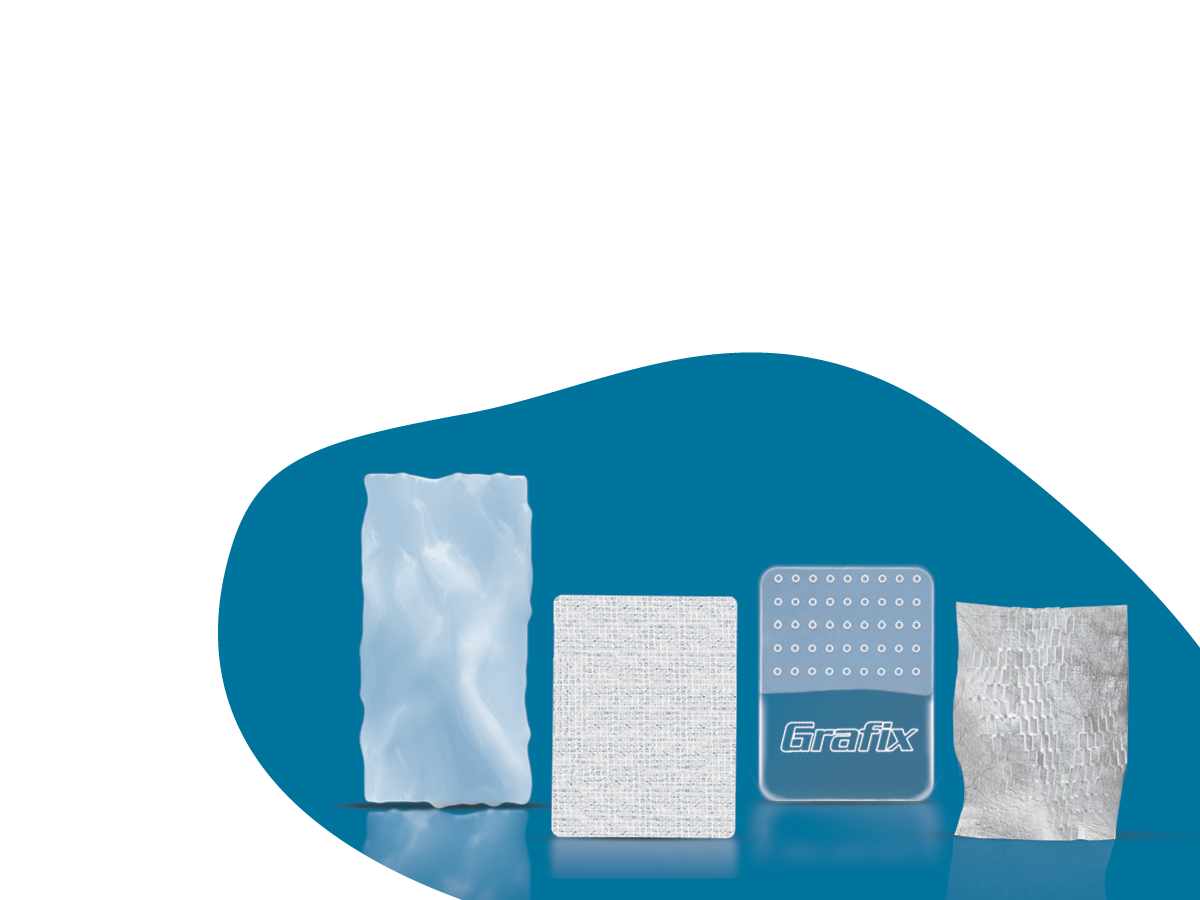

GRAFIX◊ XC

Cryopreserved Placental Membrane

GRAFIX XC Tissue brings the full power of human placental tissue—native cells and an intact extracellular matrix—directly to the wound bed.3,4

GRAFIX PL◊ XC

Lyopreserved Umbilical Tissue

GRAFIX PL XC Tissue is engineered to retain the native structure and key components of fresh human placental tissue, including an intact extracellular matrix and endogenous cells.4,5